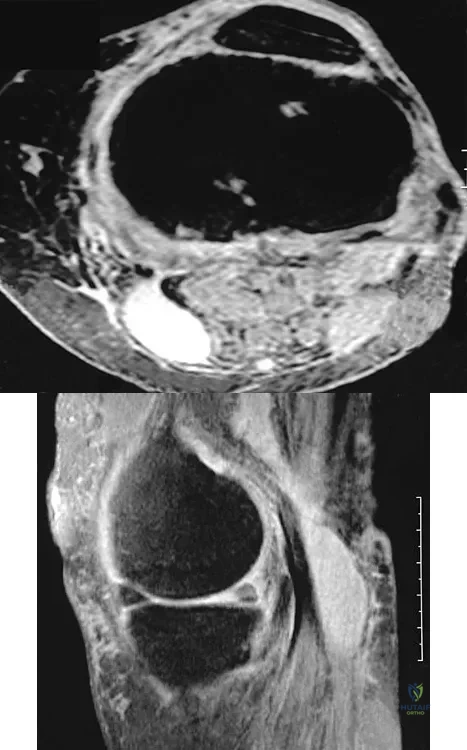

An 80-year-old woman notes a painless mass posterior to her left knee. MRI scans are shown in Figures 31a and 31b. What is the best course of action?